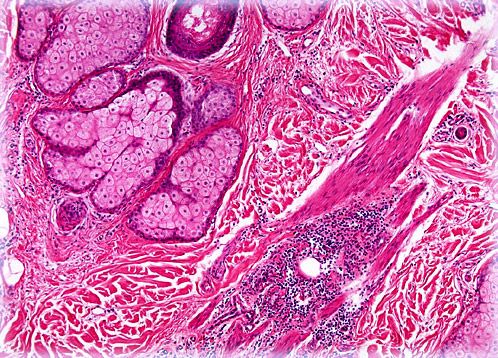

Bald Scalp

The scalp is the specialized patch of skin on the human head that is typically covered profusely in hair, containing as many as 150,000 follicles at any given time. However, genetic disposition as well as a wide array of illnesses and disorders may cause hair loss, also known as alopecia.